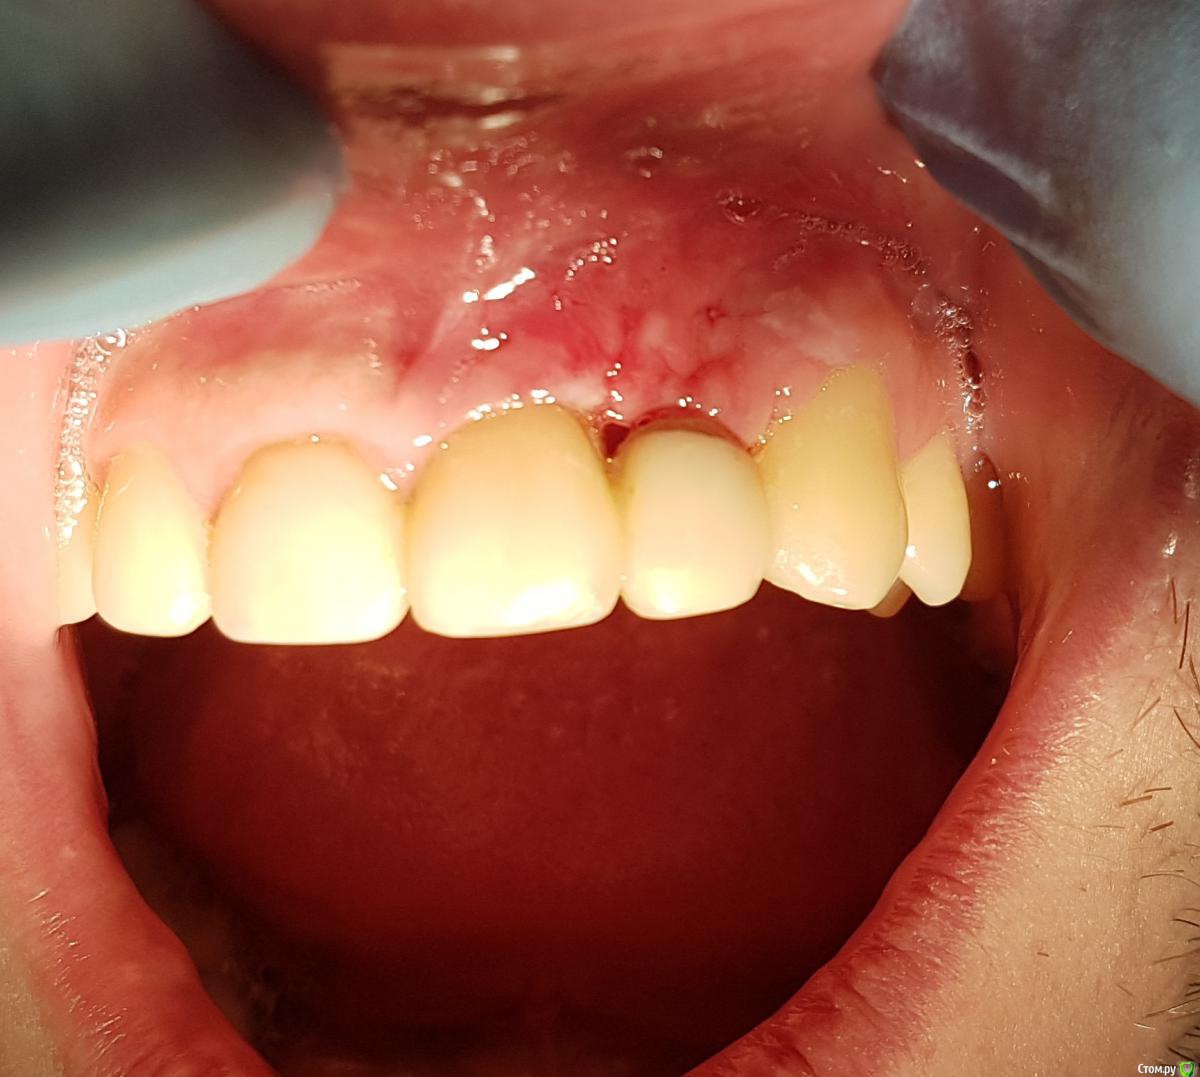

Kostoprav Опубликовано 12 июня, 2017 Автор Поделиться Опубликовано 12 июня, 2017 Ситуация во рту Ссылка на комментарий